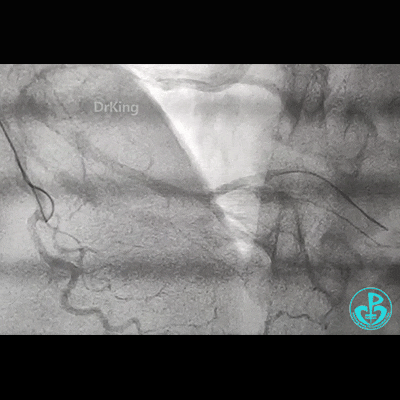

冠脉造影

右锁骨下动脉迂曲打圈,影像如下: